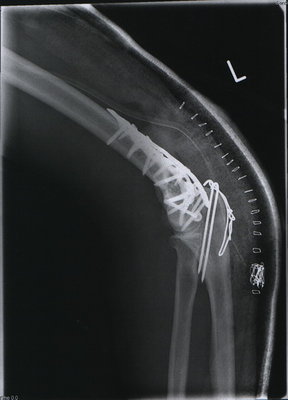

dann will ich in dem Fotothread auch mal mitmachen...

Willkommen im Titan lager...

bei mir wars am 13.2. beim Langlauf....Huuuussstt.....also ohne XT....

2010-02-19 10-32-09_0020a.jpg

2010-02-19 10-29-07_0019a.jpg

Georg, bei dir im Skelett sieht´s ja aus wie die bunte Mischung in der Werkstattwühlkiste :wink: